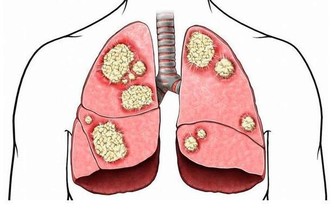

*****4..裝飾畫、木製工藝品*****有些人為了裝飾臥室,還會把一些裝飾畫、木製工藝品放在床邊。但這些木製品的加工過程中,或使用一些粘合劑,而這些粘合材料中或含超標的甲醛、苯等。以裝飾畫為例,目前很多裝飾畫的畫框採用的是中密度纖維板,也不乏一些不良商家,使用檔次較低的低密度板,甲醛、苯超標的情況很常見。而甲醛的危害性,估計不用小編多說了。作為一級致癌物,長時間接觸甲醛,致癌風險也會增加。建議:最好別把木質裝飾品放在床頭,尤其是新購置的;購買時,應選擇正規廠家出售的,買回來後,在通風處晾一段時間,待其氣味散去再放進屋子裡。除了以上這些常見的物品,睡覺前還有一些小細節也要注意——睡前牢記4個“別”,讓你睡得香、身體棒***1.別帶“濕”入睡***